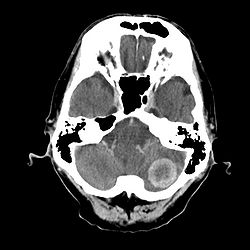

CT cerebrum

CT